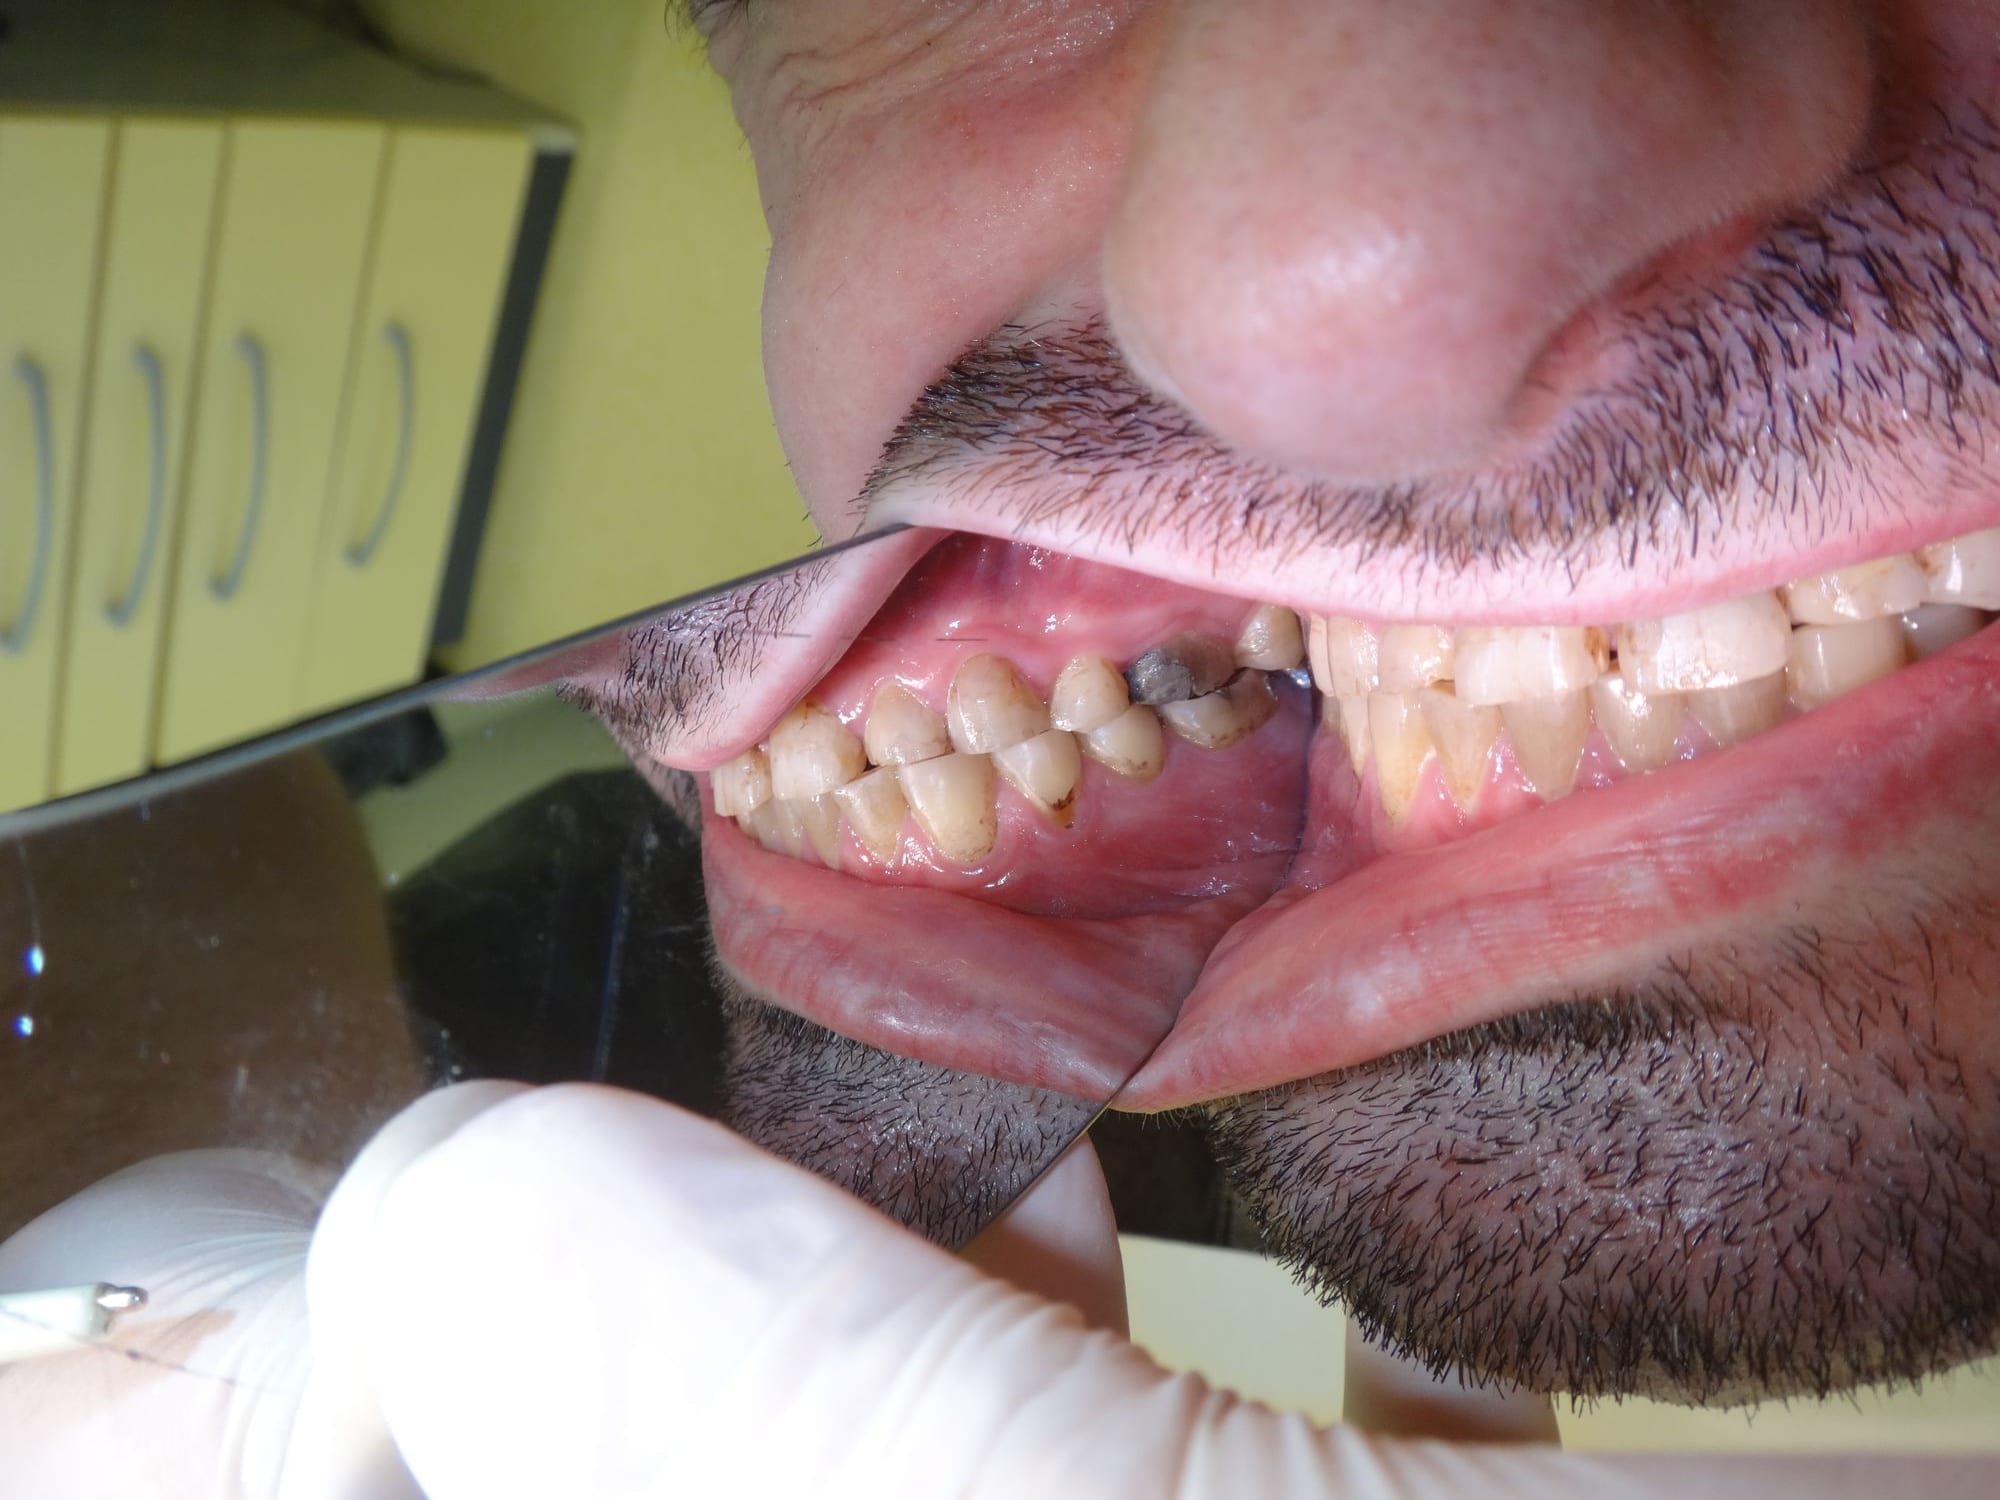

Patient 40 ans , fumeur, ex fan du coca, stressé, bruxomane forcené qui présente des érosions et abrasions chimiques généralisées.

Suite l'abrasion des dents postérieures il a une surcharge sur 11 et 21 qui sont devenues mobiles avec en plus des racines résorbées.

regarde bien la photo , il n y a aucune usure en vestibulaire des incisives du bas , rien .

ce qui veut dire que le bruxisme est latéral avec un fort appui postérieur .